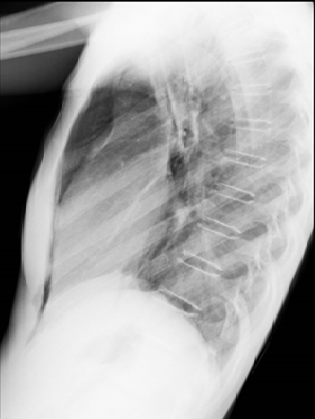

Presentamos el caso de una adolescente de sexo femenino quien cumple criterios clínicos de anorexia nerviosa y presenta dolor torácico, documentándose pneumomediastino espontáneo (PE). El PE se define como presencia de gas libre en el mediastino en ausencia de causa precipitante.

Clínicamente, el síntoma principal es el dolor torácico, seguido de disnea y a la exploración física es importante reconocer signos específicos, de los cuales el más frecuente es el enfisema subcutáneo, así como el signo de Hamman considerado patognomónico.